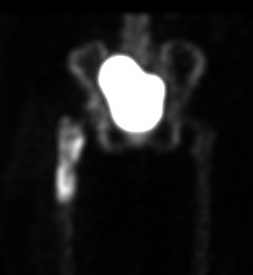

Infected THA on delayed phase

Indium 111 Labelled White cell scan + bone scan

- 64% sensitive and 78% specific for diagnosis THA infection

PET scan / [18F]Fluoro-2-deoxyglucose positron emission tomography (FDG-PET)

Kwee et al Eur J Nucl Med Mol Imaging 2008

- meta-analysis 11 studies and 600 patients

- 82% sensitive and 87% specific